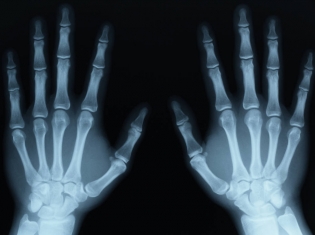

Osteoarthritis is the most common type of arthritis, which affects about 27 million adults in the United States.

The test can work from just one drop of fluid from a patient's joint. It looks for certain biomarkers that tell doctors if a patient is developing arthritis and how badly the condition will affect that patient.